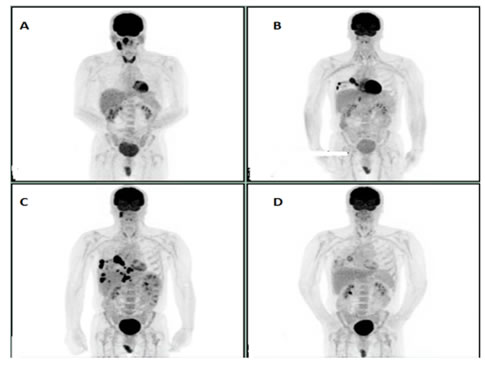

A 61-year-old female patient who was initially diagnosed with stage IV A squamous cell cancer of supraglottis, P-16 negative in November 2015. She was treated with concurrent chemoradiation with weekly Cisplatin and had a complete response in the head and neck region based on positron emission tomography (PET) scan done in June 2016. However, it showed new bilateral pulmonary nodules and right subcarinal LN and EBUS biopsy confirmed Metastatic squamous cell carcinoma. Patient was started on Pembrolizumab (anti PD-1 receptor or PD-1 inhibitor) in September 2016 which was continued until December 2016. PET scan done after four cycles of Pembrolizumab showed disease progression. Options including palliative care were discussed. She opted for more treatment options. She was started on weekly PCC (Paclitaxel/Carboplatin and Cetuximab) at that point of time given ECOG <2. She tolerated the chemotherapy very well without any Grade 3 or Grade 4 toxicities. Subsequent scans after six cycles of weekly PCC showed complete response (Figure 1A-1D).

Figure 1: A: Initial PET scan prior to chemoradiation. B: PET scan prior to initiation of Pembrolizumab. C: PET scan showing progression after 4 cycles of Pembrolizumab. D: Complete response after 6 cycles of weekly PCC.